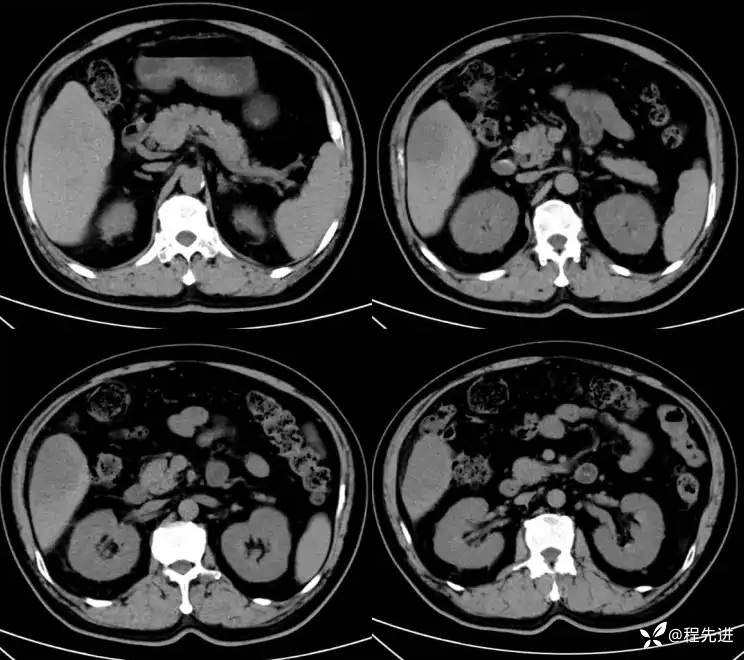

CT平扫:

动脉期: